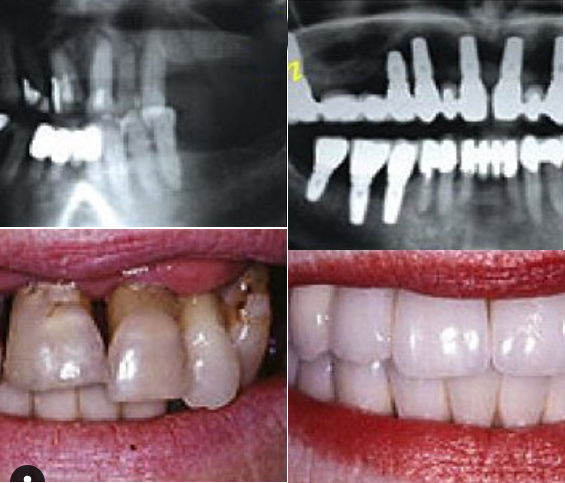

إذا كنت ترغب في الحصول على أسنان ولا تملك ما يكفي من العظام لإجراء علاج الزرع، لم يعد هناك حاجة إلى زراعة العظم من الآن فصاعدا.

تقدم زراعة الأسنان تحت السمحاق ثلاثية الأبعاد (3D subperiosteal implants) حلاً موثوقًا للحصول على أسنانك، خاصة في الحالات التي تكون فيها كمية العظام غير كافية لدعائم الزرع التقليدية.

عوده دون الحاجة إلى الخضوع لعلاج ترقيع عظمي واسع النطاق.

هذه التقنية ثورة في استبدال الأسنان!